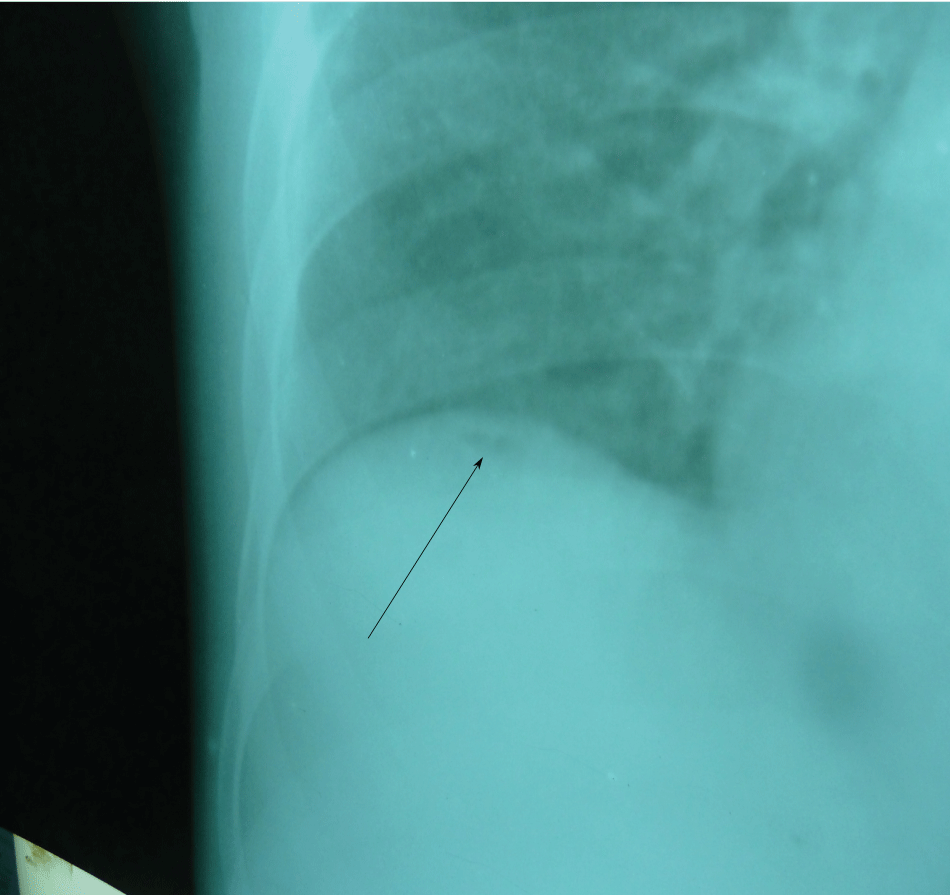

Figure 2: The right side of the chest X-ray showing small air bubble (arrow) below the right hemidiaphragm.

Baseline full blood count investigations showed a haemoglobin concentration of 11.3 g/dl, total white blood cell count of 6900 cells/μl (lymphocyte 11.5%, neutrophil 80.3% and mixed cells of 8.2%). Malaria parasite and sickling status proved negative. Alanine transaminase (ALT) and aspartate transaminase (AST) were marginally raised and the total protein was slightly low although serum albumin was markedly reduced (22.0 g/dl). Chest X-ray showed minute pneumoperitoneum below the right diaphragm (Figure 2).